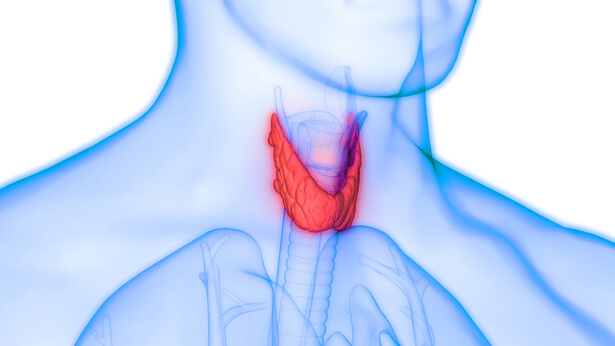

Glande mal connue, la thyroïde est pourtant un régulateur hormonal important. En cas de dérèglement, les conséquences sur le corps humain sont nombreuses. Les problèmes de thyroïde sont de plus en plus fréquents : il peut s’agir de dérèglements de type maladies auto-immunes, le plus souvent provoquées par l’âge, certains polluants ou perturbateurs endocriniens, mais également par des carences (en iode notamment).

Examen de la thyroïde © Goncharov_Artem

Glande thyroïde © Magic mine